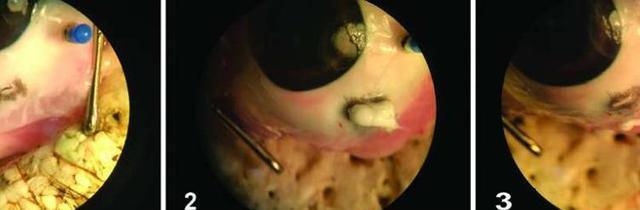

圖片來(lái)源:Science Translational Medicine (2017)

當(dāng)醫(yī)生準(zhǔn)備手術(shù)時(shí),水凝膠可以通過(guò)冷卻水轉(zhuǎn)化到低粘狀態(tài)。